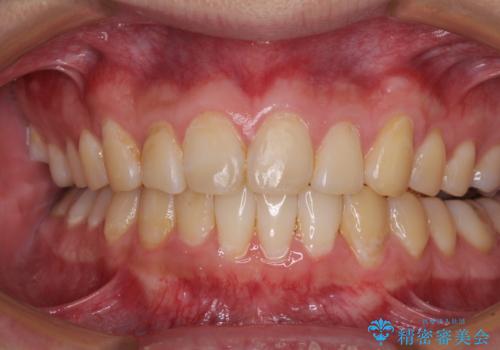

- 上下前歯のデコボコを気にして来院された患者様です。

前歯のデコボコ以外に左側の奥歯の咬み合わせに問題がありましたが、価格を抑え、短期間で気になる前歯を治したいとのことでした。

こちらの患者様は、事前のシミュレーションにより、インビザライン・ライトでは前歯のデコボコを解消しきれないことが分かったため、通常のインビザライン(コンプリヘンシブパッケージ)での治療が必要となりました。

しかし、費用面や期間で悩んでいらっしゃったため、左側臼歯の問題は解決せずに前歯のデコボコのみを改善するシミュレーションを作成し、治療を行うこととしました。

写真より左側臼歯の咬合がタイトではないことが分かりますが、こちらは保定期間に徐々に咬合させていくこととしました。